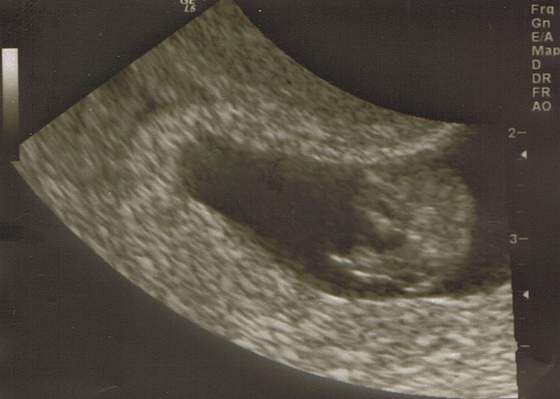

Citrus 27 mm (prawie 3 cm)

No dumna jestem strasznie.

Zstanawiam się tylko, czy to normalnie na tym etapie, że głowa jest taka duża

Zapominajka - jakie piękne dziecko! Aż mi się łezka kręci.... A u mnie tylko pęcherzyk ;-)

Za kilka tygodni i twój maluszek tak będzie wyglądał.

Zapominajka, Fiołkowa - super fotki z USG, gartuluję! Mam nadzieję, że za 2 tyg. też ujrzę podobną